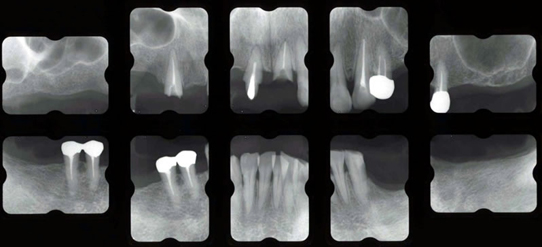

治療前

上下の奥歯がないまま10数年たっていました。前歯に負担がかかりついには上の前歯が脱落してしまいました。前歯だけを治療してもまた壊れてしまいます。奥歯をしっかり咬めるようにすることが大事です。